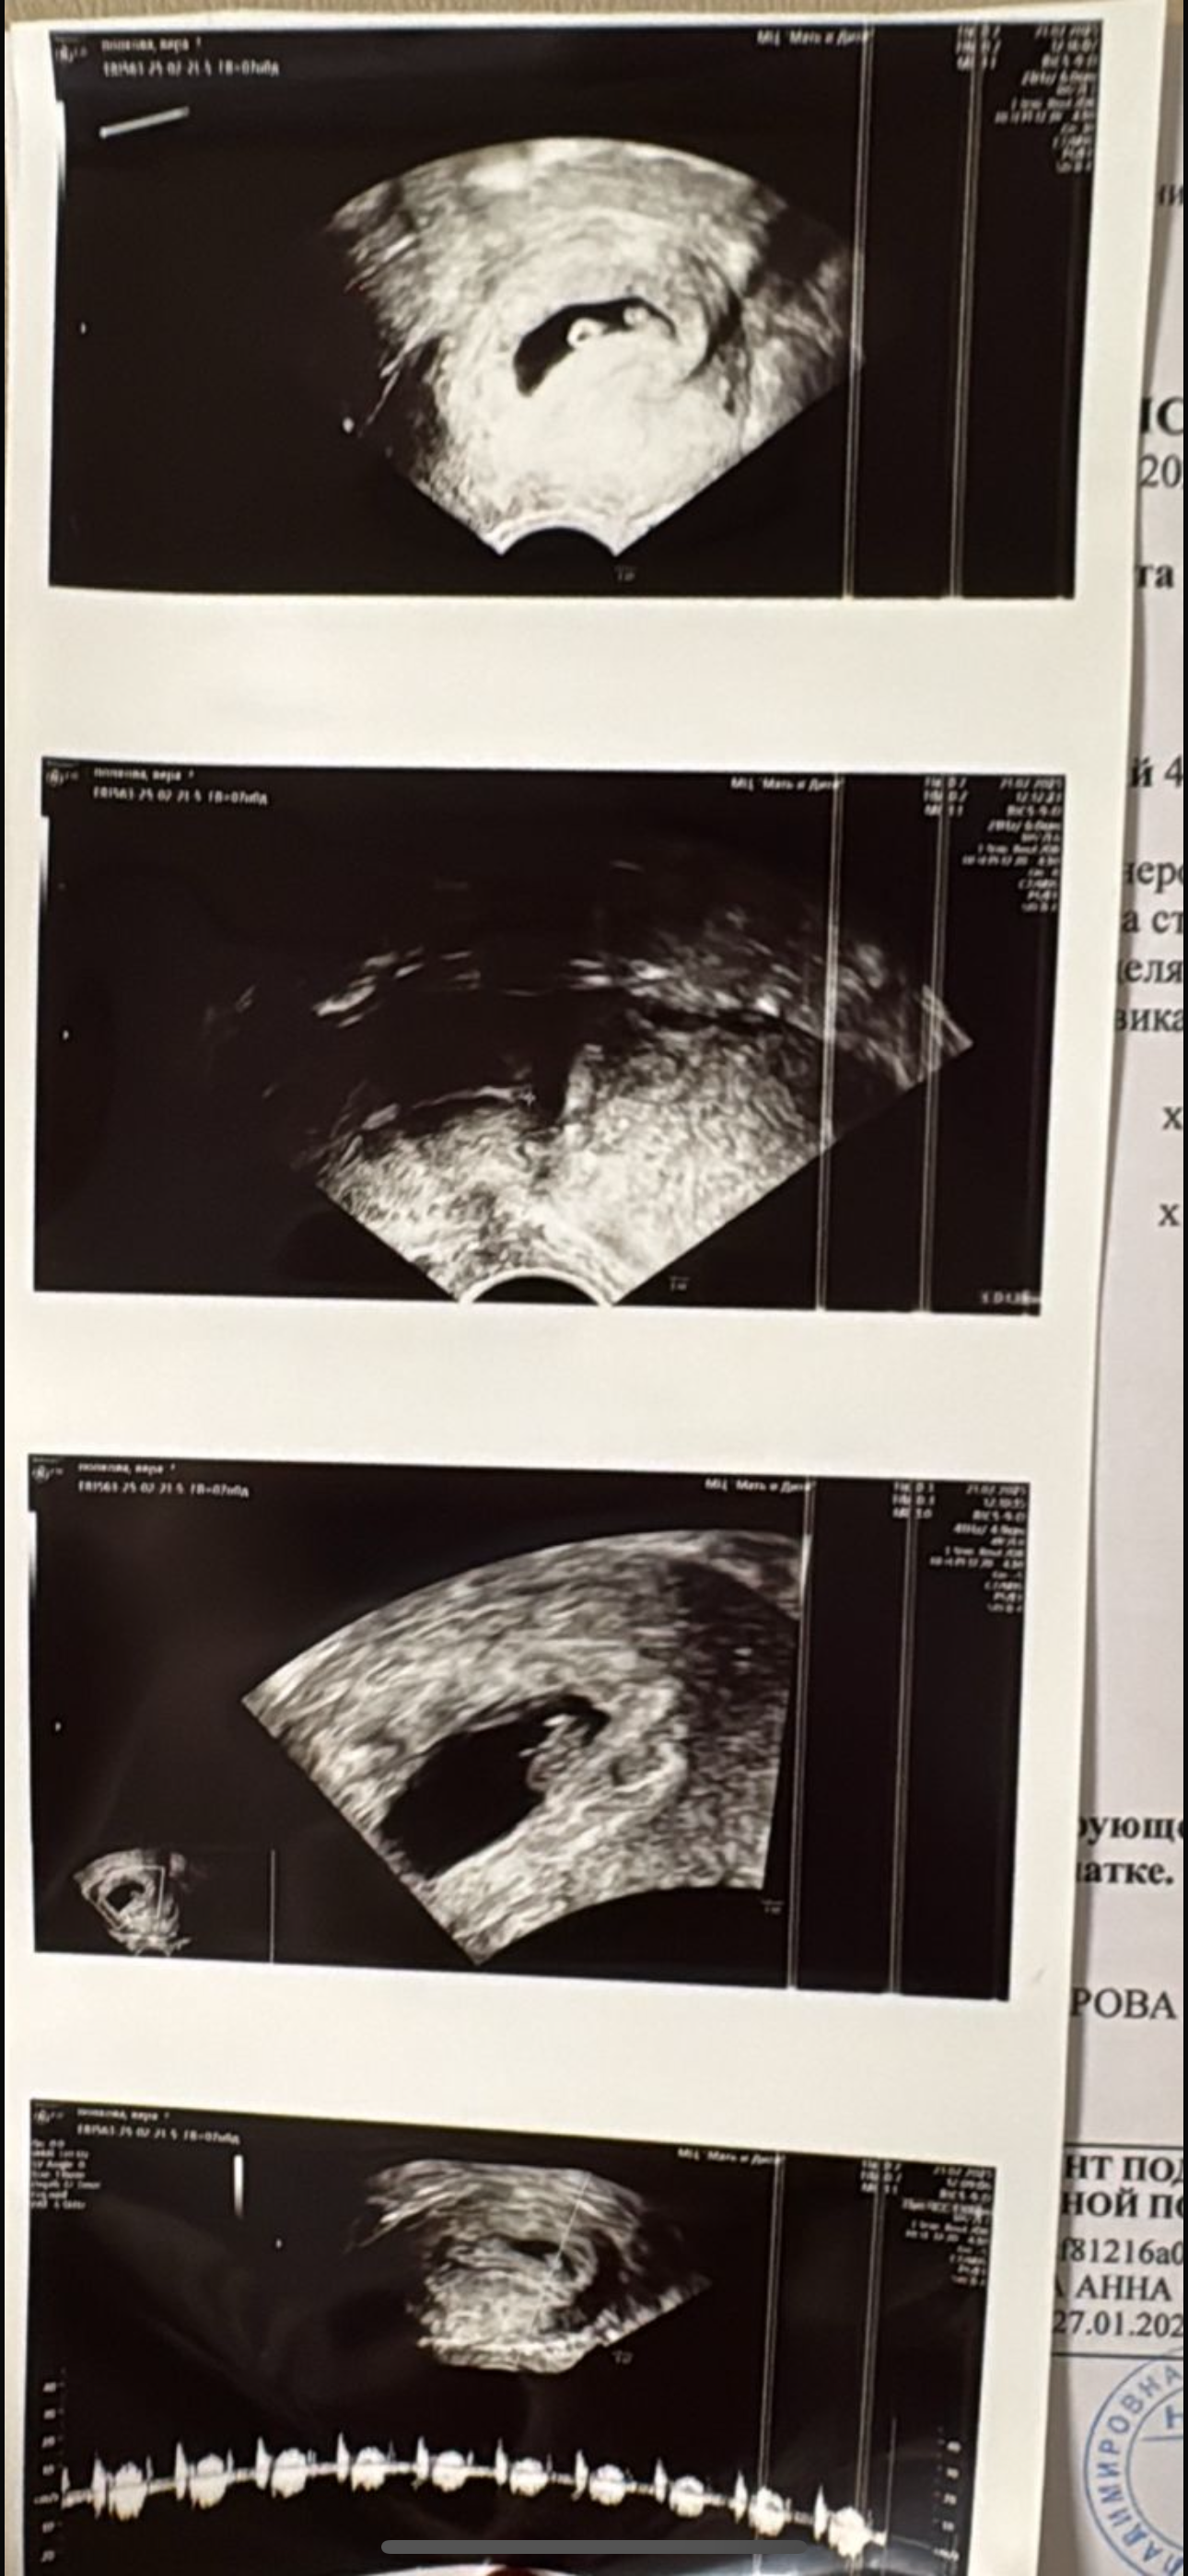

Результаты УЗИПривет, девочки! Не выдержала, сходила на УЗИ, так как на прием записали только на 04.03.25. вобщем, все хорошо, наш малыш подрос и развивается 🙏🙏🙏. Срок 6-7 недель, сердечко бьется